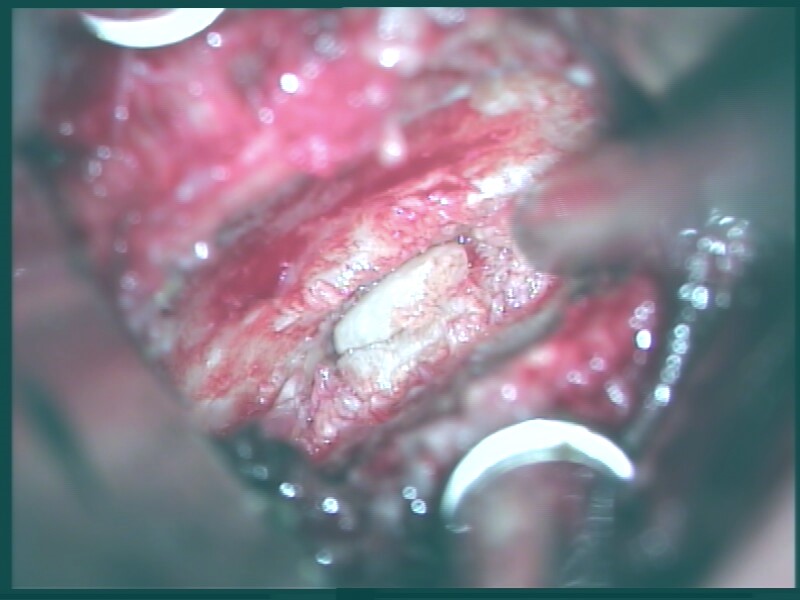

Approximately 95 % of all operational interventions on the cervical spine are made from the front. During this operation which is made with the help of general anaesthesia, a small section which has a size of approx. 4 cm will be made which is localized at the right side of the neck. Due to this procedure it is possible to disclose the vertebral column. With the help of a surgical microscope the doctor is going to extract all osseous stenosis with a diamond milling cutter out of the spinal disk. After that procedure the spinal disk will be stabilized by an implant which is made up of titan or plastic. In special cases it could be necessary to use an entire spinal-disk-implant.